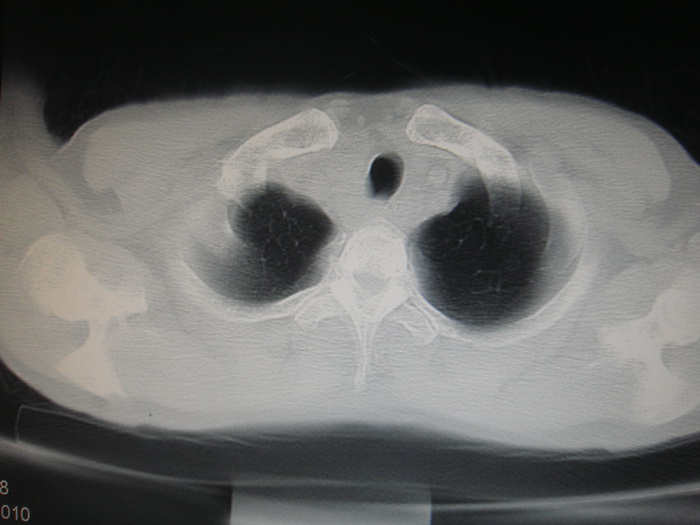

标题: CT28366:男性,45岁,偶尔发现右颈部肿块行胸部CT扫描。 [打印本页]

男性,45岁,偶尔发现右颈部肿块行胸部ct扫描。

两肺多发结节灶及纵膈淋巴结肿大考虑为转移

两肺多发性转移瘤,纵隔淋巴结转移。

两肺多发性转移瘤,纵隔淋巴结转移。食道中上段管壁似乎增厚,作相关检查。

两肺多发性转移瘤,前上纵隔淋巴结转移。